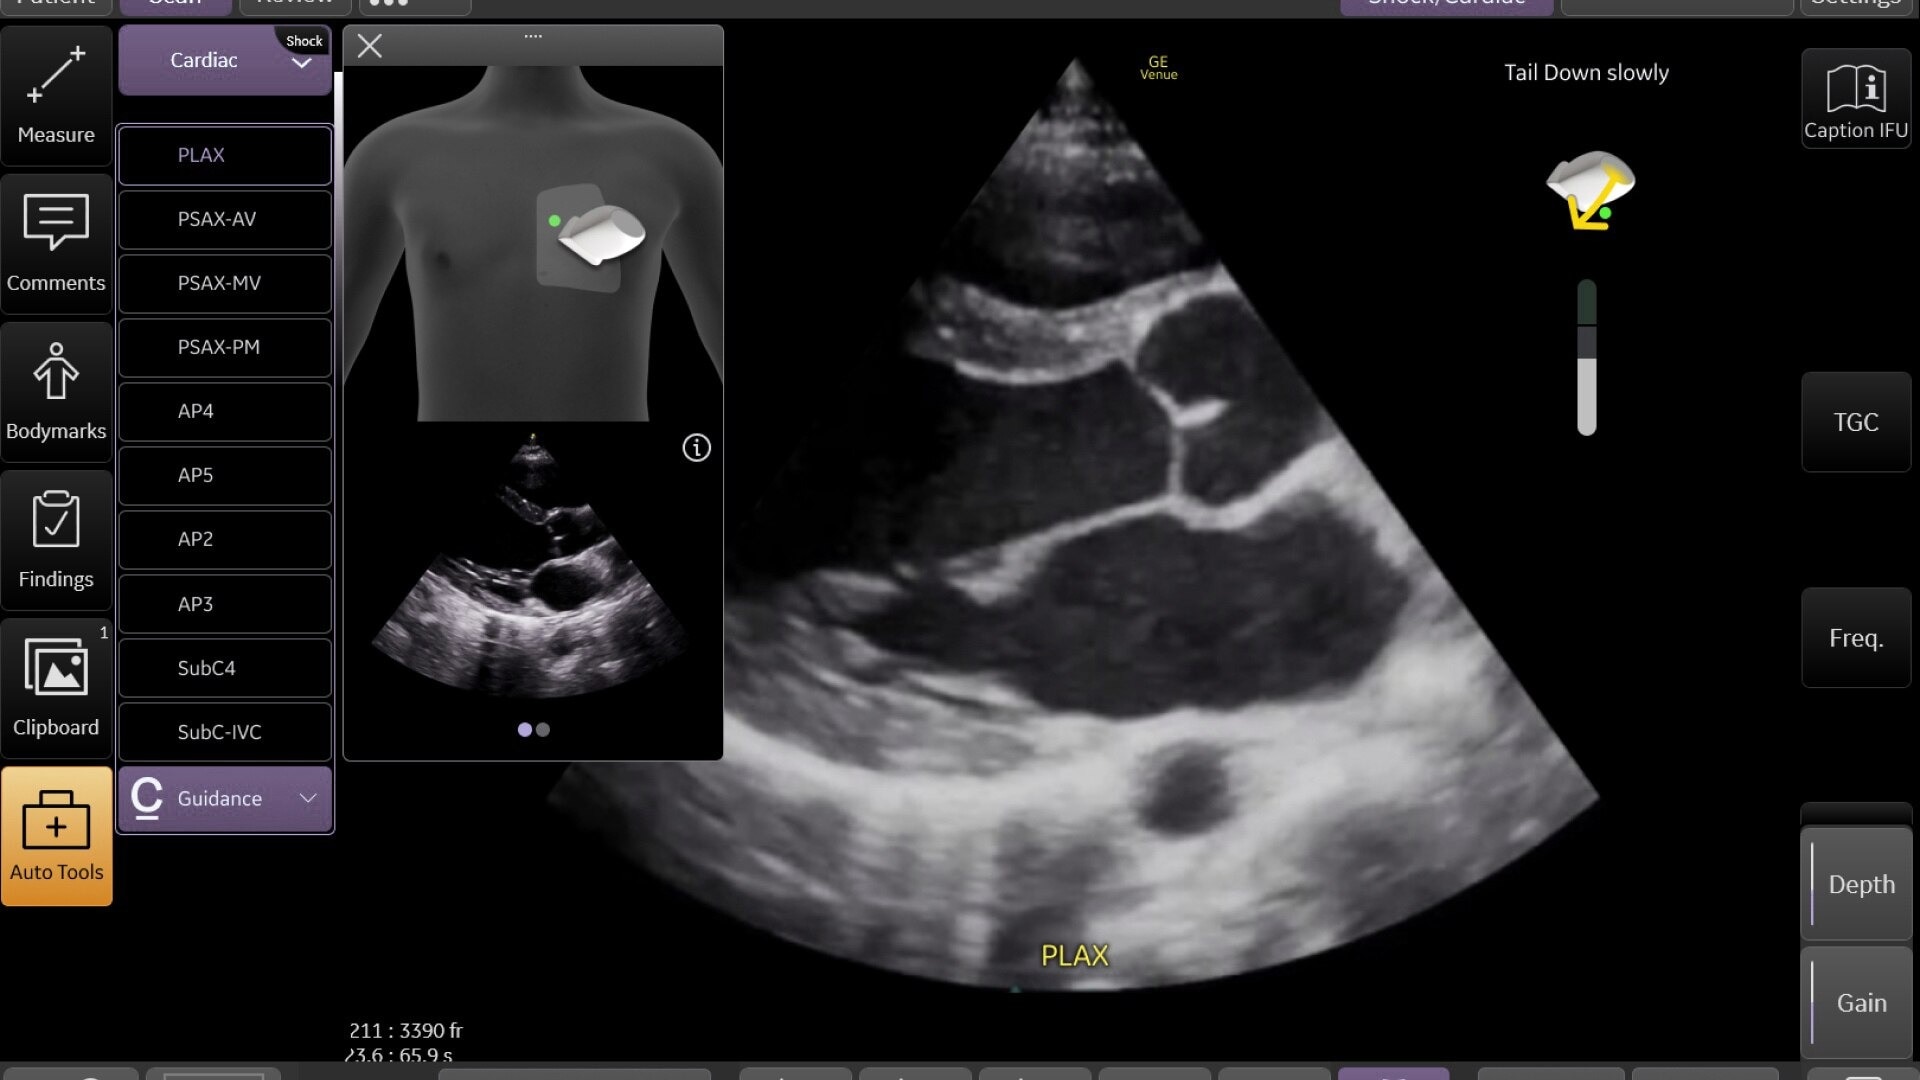

Wireless probe integration

Sync up and go - without wires you’re not tethered to a system or a space

Small yet powerful

Flexible, wireless dual-probes deliver clear images and Venue family software